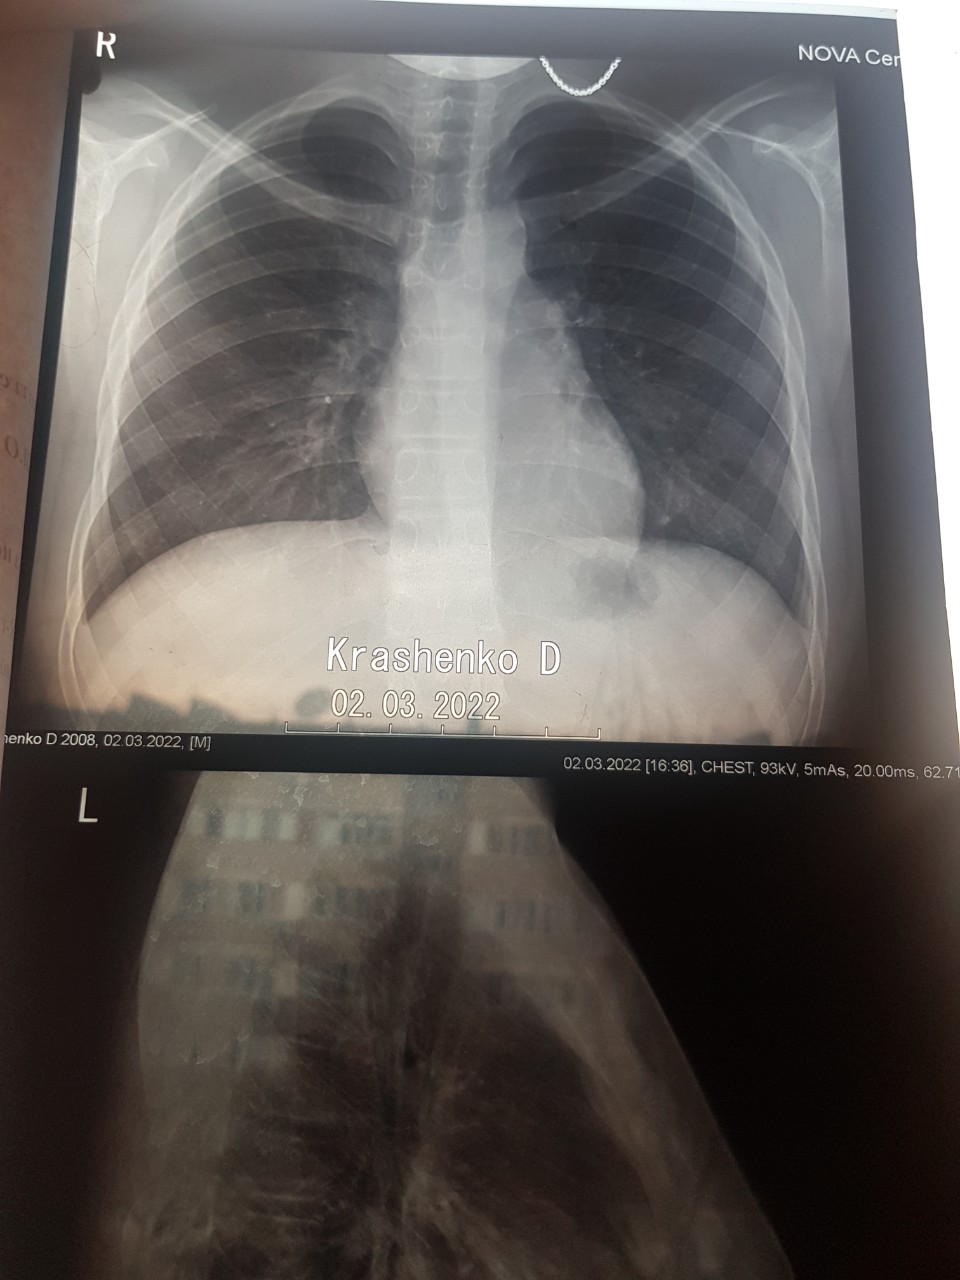

Медицина и диагностика: Аномалии ребер на рентгене

.jpg)